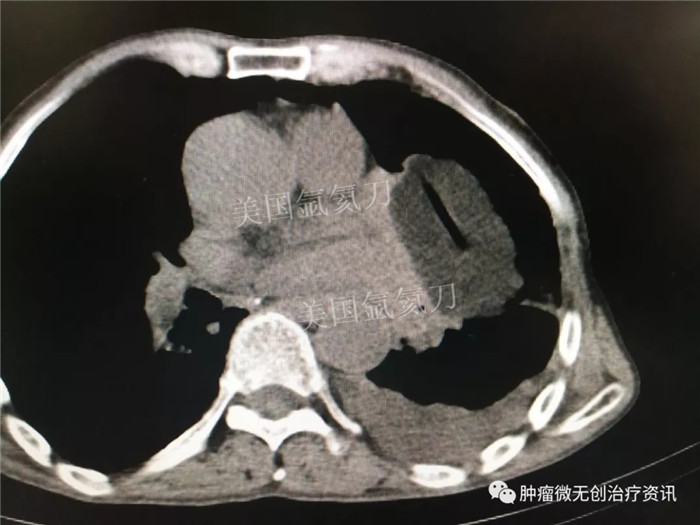

郑州大学附属郑州中心医院氩氦刀冷冻消融治疗肺部肿瘤

67岁老年男性患者,因肺部肿瘤,于7月28日行氩氦刀冷冻消融治疗。